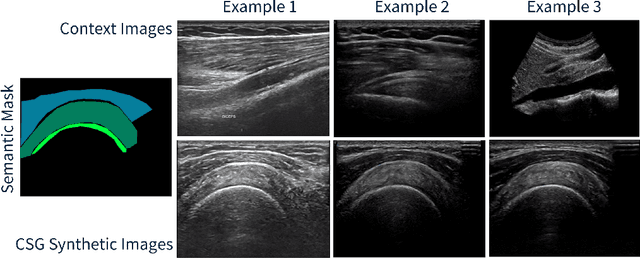

Abstract:The use of synthetic images in medical imaging Artificial Intelligence (AI) solutions has been shown to be beneficial in addressing the limited availability of diverse, unbiased, and representative data. Despite the extensive use of synthetic image generation methods, controlling the semantics variability and context details remains challenging, limiting their effectiveness in producing diverse and representative medical image datasets. In this work, we introduce a scalable semantic and context-conditioned generative model, coined CSG (Context-Semantic Guidance). This dual conditioning approach allows for comprehensive control over both structure and appearance, advancing the synthesis of realistic and diverse ultrasound images. We demonstrate the ability of CSG to generate findings (pathological anomalies) in musculoskeletal (MSK) ultrasound images. Moreover, we test the quality of the synthetic images using a three-fold validation protocol. The results show that the synthetic images generated by CSG improve the performance of semantic segmentation models, exhibit enhanced similarity to real images compared to the baseline methods, and are undistinguishable from real images according to a Turing test. Furthermore, we demonstrate an extension of the CSG that allows enhancing the variability space of images by synthetically generating augmentations of anatomical geometries and textures.